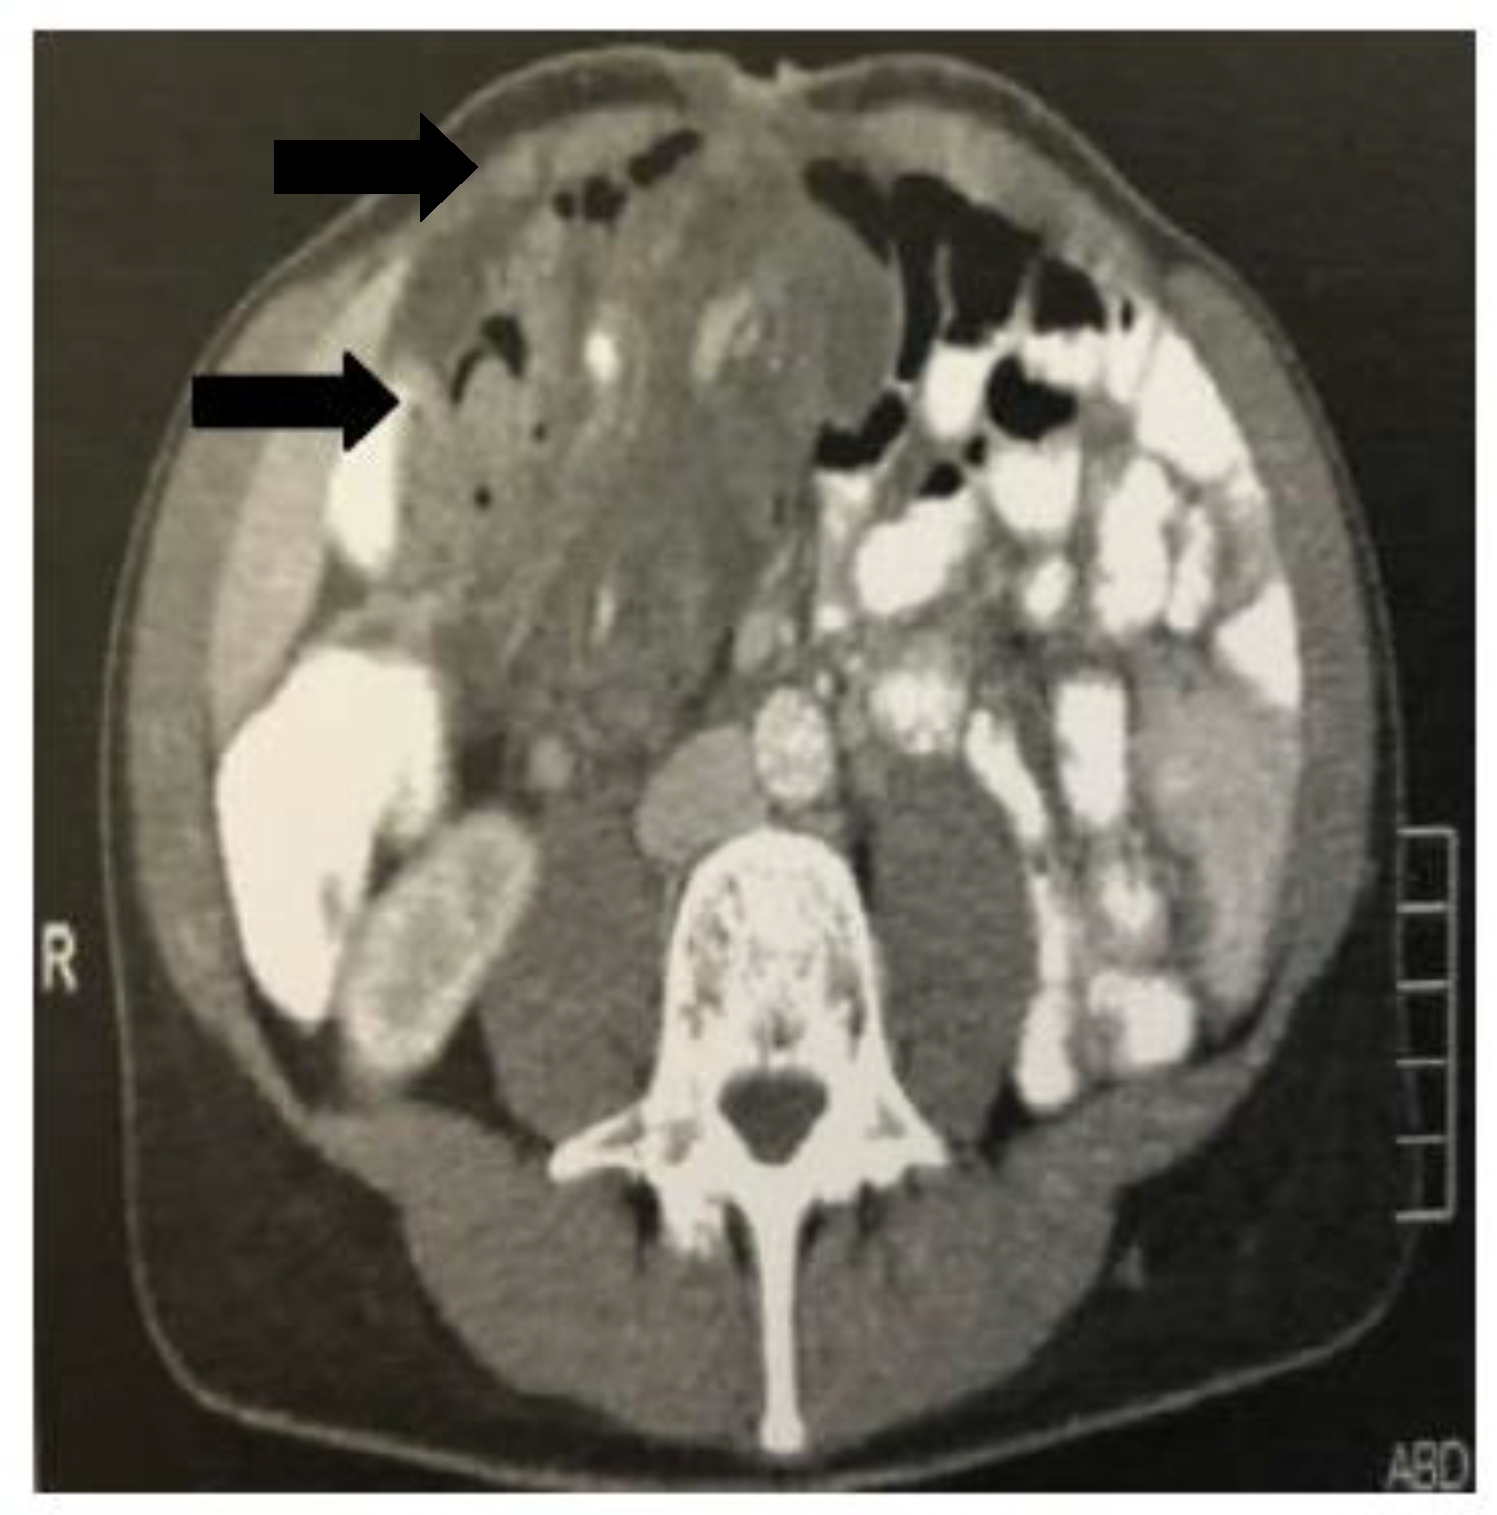

The first case concerned a 48-year-old female patient, who presented to the emergency department with diffuse abdominal pain over the last 24 hours and vomiting. Her medical and surgical history were free. The laboratory results showed an elevated White Blood Cell (WBC) count (17.4 mm3/μL, normal range 4.3-10.3 mm3/μL) and a normal C-Reactive Protein (CRP) value (0,4 mg/dL, normal range < 0,5 mg/dL). Plain abdominal imaging in an upright position revealed air fluid-levels typical for an intestinal obstruction (Figure 1a), whereas the ultrasound examination was non-conclusive. The computed tomography (CT) scan showed a distention of the small intestine until the terminal ileum, without identifying the cause of obstruction. Initially, a nasogastric tube was placed for conservative management. After 48 hours the patient’s condition as well as the plain abdominal imaging (Figure 1b) showed no signs of improvement, so an exploratory laparotomy was decided.

Figure 1. plain abdominal radiograph of the patient (first case) in an upright position, on admission (a) and 48 hours later (b). Air -fluid levels (black arrows) typical for small bowel obstruction are clearly seen in both films, with no signs of improvement after conservative treatment with nasogastric tube (white arrow).